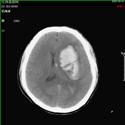

颅脑损伤——开展重型颅脑损伤的大骨瓣减压、后颅窝血肿清除减压、人工硬膜修补、矢状窦破裂修补、凹陷骨折整复、快速气管切开术;亚低温治疗,成功的挽救多名危重患者的生命。后期联合高压氧治疗、钙离子拮抗剂、促醒药物治疗、颅骨修补手术和康复治疗多种方法结合提高患者的生存率和生存质量。总结出重型颅脑损伤有效和规范的治疗方法。

1).硬膜外血肿 术前 术后

2).颅后窝血肿术前 术后

3).颅骨凹陷性骨折术前 术后